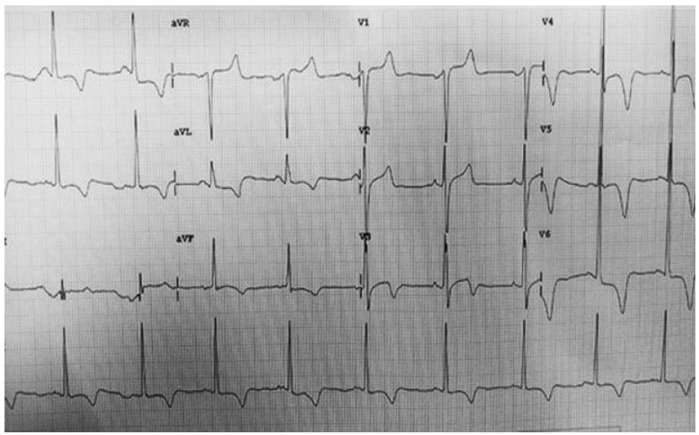

Paciente, sexo masculino, 60 anos, dá entrada na Unidade de Pronto Atendimento, a qual você estava de plantão, com queixa de precordialgia típica, em aperto, iniciada há cerca de 2 horas. AMP: HAS, DM2, Acidente vascular hemorrágico há 10 anos. Em uso: Atenol 25 mg, Hidroclorotiazida 25 mg/dia, Losartana 50 mg 12/12h. Exame físico: Eupneico em ar ambiente, Sat O2 98%. Ausculta cardíaca: bulhas cardíacas normofonéticas 2 tempos, sem sopros. Ausculta Pulmonar: Murmúrio Vesicular Presente Bilateralmente, sem ruídos adventícios. Sem edemas, Tempo de enchimento capilar > 3 segundos. Realizado eletrocardiograma em até 10 minutos:

Enunciado 4376247-1

Fonte: https://tracadosdeecg.blogspot.com/2016/08/como-diferenciar-sca-com-supra-de-st-da.html

Nesse local que você trabalha, não dispõe de serviço de hemodinâmica, e para chegar ao hospital de referência cardiológica, para realização de tal exame, demora-se cerca de 2 horas e meia. A conduta que deve ser tomada nesse contexto, a fim de reduzir mortalidade é: